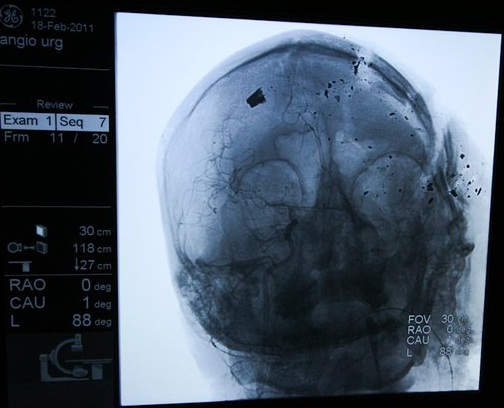

صورة من الأشعة للشهيد عبدالرضا بوحميد... رصاصة قاتلة |

الحالة الأشد صعوبة هي حالة عبدالرضا بوحميد (38 عاماً)، أصيب رصاصة حية في الجمجمة، الاستشاري نبيل حميد يحاول إنقاذه، عملية جراحية تستمر ثلاث ساعات، دون أن تتمكن من إخراج الرصاصة من رأس عبد الرضا. الاستشارية نهاد الشيراوي تعمل على متابعة حالته. يبقى فيما يشبه الموت السريري ليومين، قبل أن يفارق الحياة في 21 فبراير، وقبل أن تنهار الشيراوي باكية أمام عدسات التصوير، ولتدفع بعدها، في المحاكم العسكرية، ثمن هذا البكاء من أجل حياة إنسان.